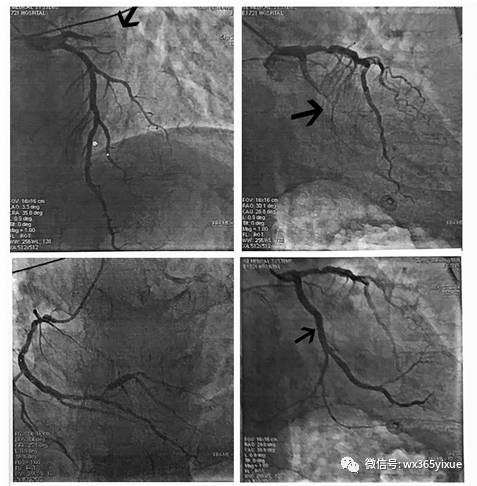

心电图是临床判断下壁梗死相关血管的最重要手段。虽然方法比较多,但Fiol四步法更具有实用性和系统性(见图4)。一旦确定下壁心肌梗死由回旋支闭塞引起,更应该进一步排查是否合并正后壁或其他侧壁心肌梗死。

图4  Fiol四步法